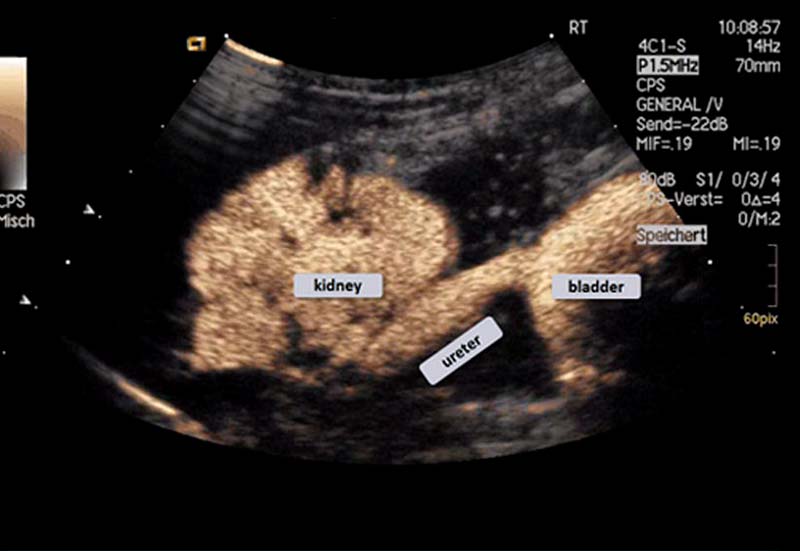

Ultrasound contrast agents allow the display of the excretory urinary tract and the demonstration of vesicoureteral reflux of urine from the bladder up to the kidney in children.

For the assessment of urinary reflux the bladder is filled with physiological saline solution and a small amount of microbubble contrast agent is added to make the fluid in the bladder echogenic. The distribution and potential reflux of the bladder content can be assessed after instillation and during subsequent micturition, creating an increased pressure in the bladder.

The urine reflux can be graded using the scale below:

grade I: reflux into the ureter, not reaching the renal pelvis

grade II: reflux reaches renal pelvis, without dilatation of the ureter

grade III: mild dilatation of the renal pelvis, with no significant changes of the renal calix

grade IV: moderate dilatation of the renal pelvis, renal fornix blunted but papillary impressions still visible

grade V: strong dilatation of the ureter with kinking, pelvicalyceal system highly dilated, loss of papillary impressions